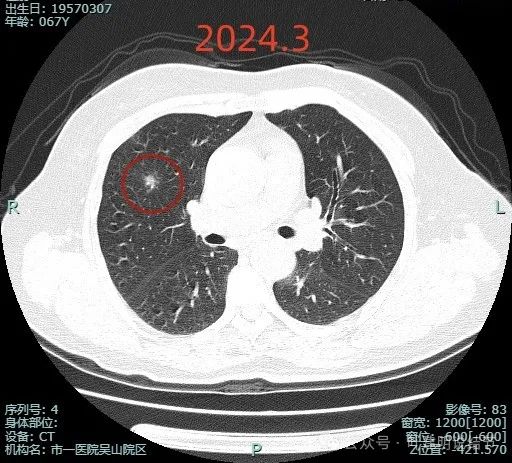

先来看病灶较大层面不同时期的影像:

这是2024年3月时的平扫影像,密度不纯,表面不平,整体轮廓较清。